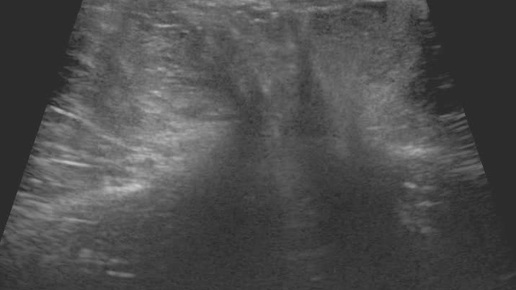

Видео к статье "Общие принципы ультразвуковой диагностики наружных грыж живота" Адрес: https://dzen.ru/a/Z2k58ScRsjQP-dA9